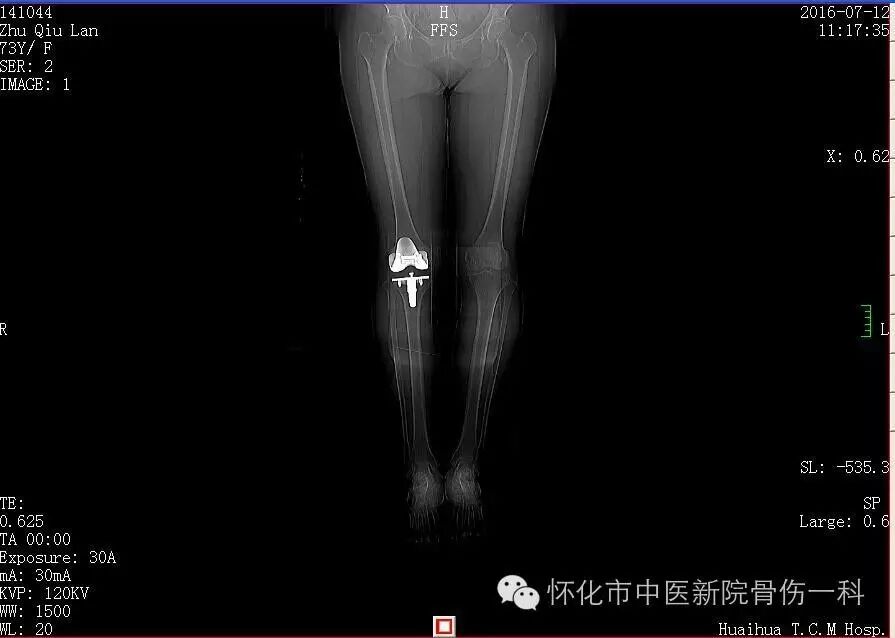

患者:朱某  性别:女    年龄:73岁   病程:10年以上

诊断:1.右膝关节退行性病变

2.痛风

3.冠状动脉粥样硬化 慢性冠脉性心绞痛型 心功能二级

4.高血压三级 高危组

手术前情况:行走受限,活动痛加重。右膝关节肿胀,疼痛,活动受限,右下肢轻度浮肿,右膝关节屈曲度:屈:110°-150°;伸:30°-70°。患者完全无法进行正常的行走,生活不能自理。

手术方式:右膝全髋关节置换术

术前片: